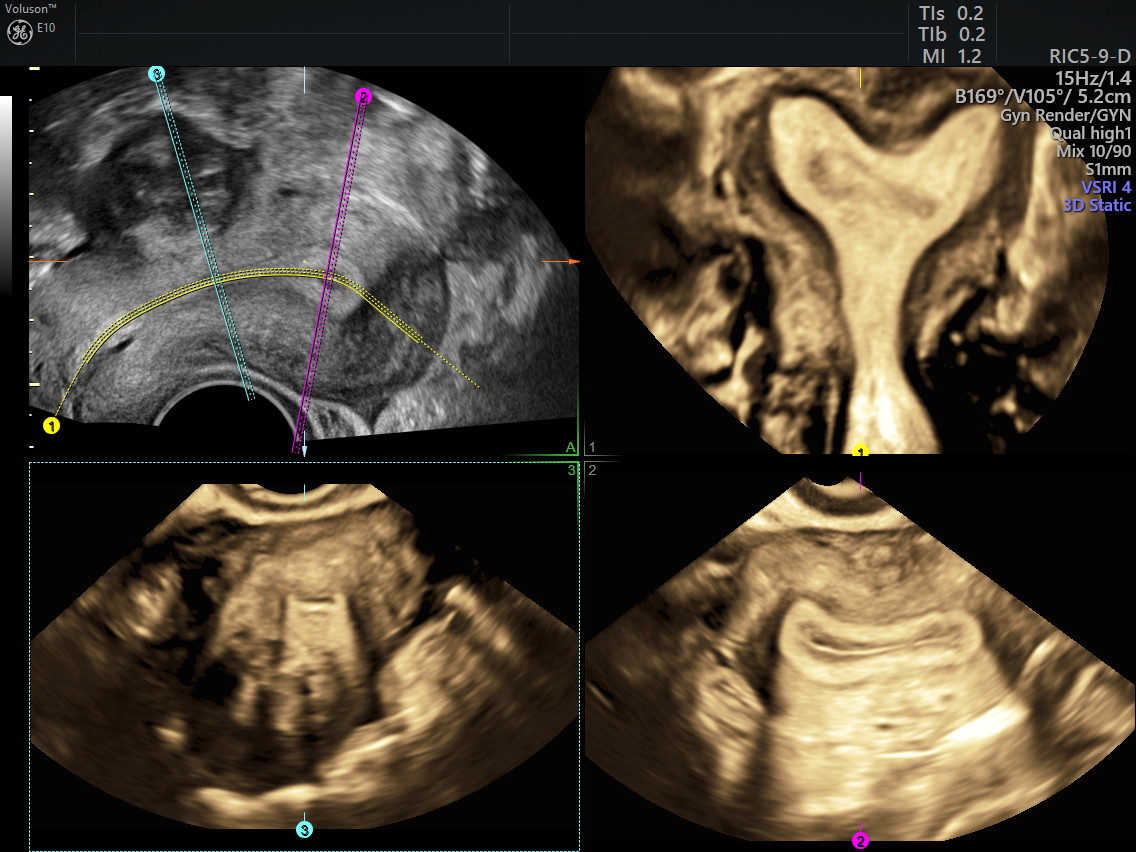

Imagens de ultrassom 3D

Útero Normal

Útero Unicorno

Útero Arqueado

Útero com Septo Longitudinal Parcial

Útero com Septo Longitudinal Completo

Útero em forma de letra T (“T Shapped”)